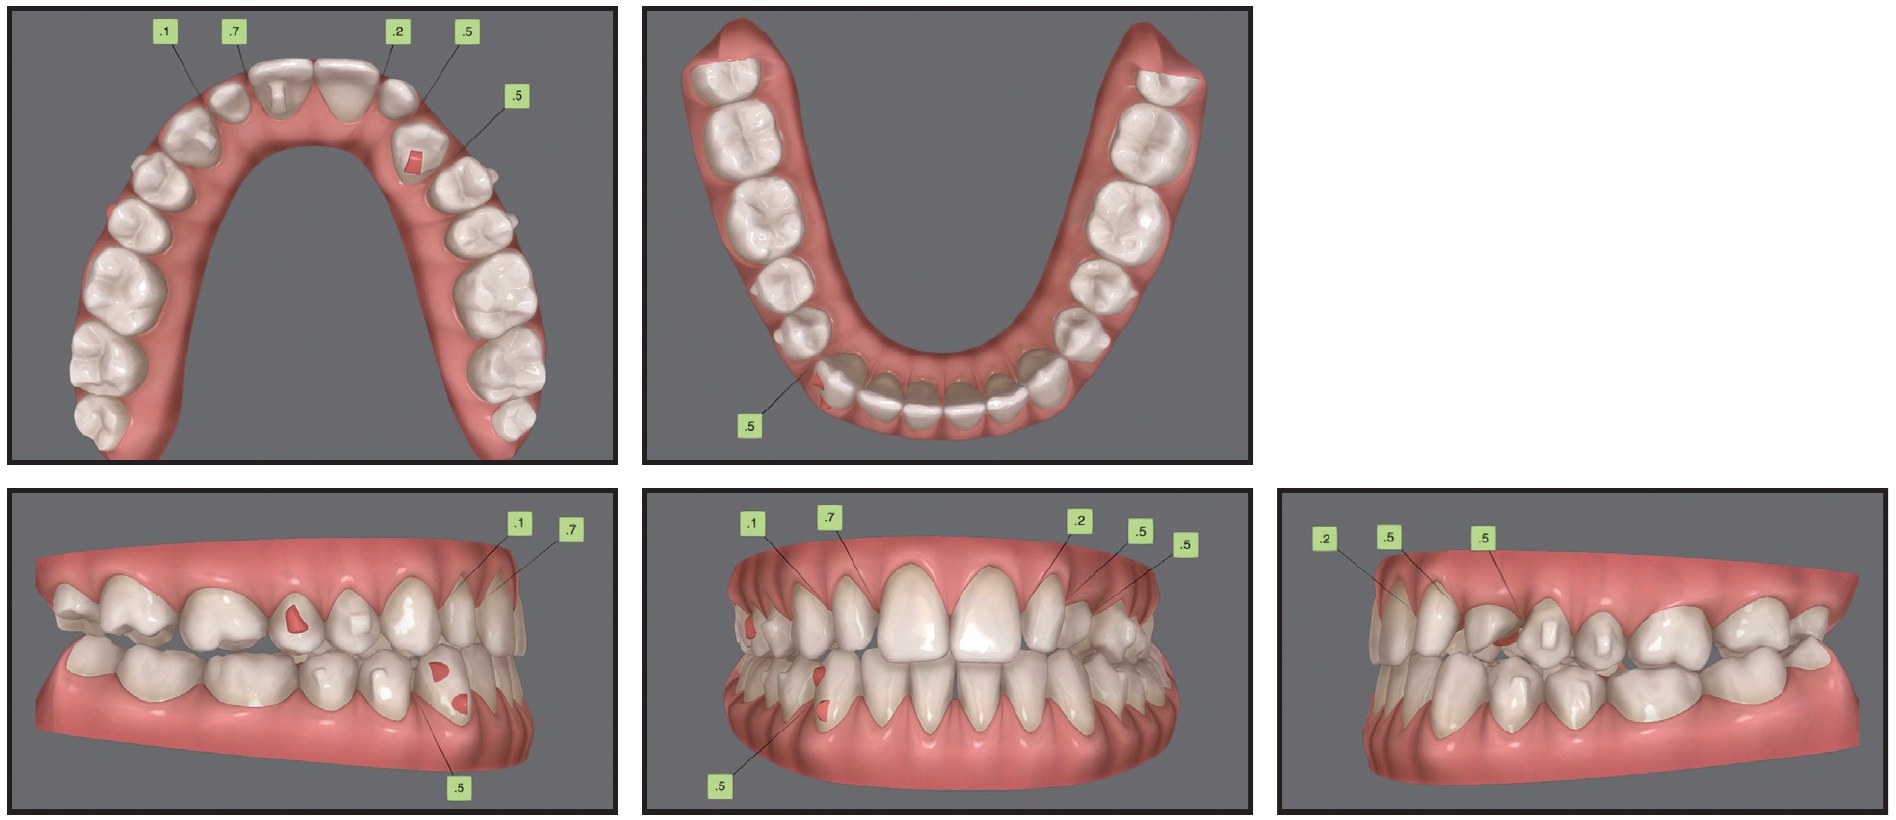

Case 3: Applying Traction Forces with Different Vectors

A 29-year-old male presented with the chief complaint of a gap between his upper front teeth (Fig. 11). The soft-tissue profile was straight, with mildly retrusive upper and lower lips, 50% incisor display in smiling, and a flat smile arc. The mandibular midline was deviated 3mm to the left of the facial midline, and there was a 2mm diastema between the upper central incisors; the overbite was 1-2mm. Class III molar and canine relationships were present on the right side, and Class I relationships on the left. The maxillary arch was constricted compared to the mandibular arch, with a crossbite from the left canine to the left second molar. The lower left deciduous canine was retained, and mild crowding was noted in the mandibular arch. The upper right lateral incisor was in an edge-to-edge relationship with the lower right canine, while the upper left incisor was in an anterior crossbite. Bolton analysis indicated a 2.07mm mandibular excess due to the narrow mesiodistal width of the upper lateral incisors (6mm each).

Fig. 11 Case 3. 29-year-old male patient with horizontally impacted upper left canine, diastema between upper central incisors, Class III molar and canine relationships on right side, left buccal crossbite, and Bolton discrepancy before treatment.

The panoramic radiograph revealed that the upper left canine was horizontally impacted, overlapping the root of the upper left lateral incisor. Cephalometric analysis indicated a Class III skeletal relationship (ANB = –1°, Wits appraisal = –3mm) with a normal vertical dimension (MPA = 34°). Both the upper and lower incisors were retroclined.

Treatment objectives were to bring the impacted canine into the arch and obtain Class I molar and canine relationships, along with a normal overjet and overbite. The Bolton discrepancy would be addressed with porcelain veneers on the upper lateral incisors. The goals of clear aligner treatment (see box) were to expand the maxillary arch, procline the incisors, close the space between the upper central incisors, prepare space in the arch for the impacted canine, and correct the Class III relationship and midline deviation, using Class III elastics for bite stimulation (Fig. 12).

After 30 months of treatment, involving 27 sets of aligners for the initial treatment and five sets for refinement, changed every two weeks, the left canine was fully aligned, and proper torque and root parallelism were obtained, with no signs of root resorption noted on the panoramic radiograph (Fig. 15). The upper lateral incisors were restored with porcelain veneers. The appearance of the smile had improved, with increased incisor display. The lower midline was coincident with the facial midline, and Class I canine and molar relationships were achieved.

Fig. 15 Case 3. Patient after 30 months of treatment, showing aligned upper left canine, Class I canine and molar relationships, and improved smile appearance.